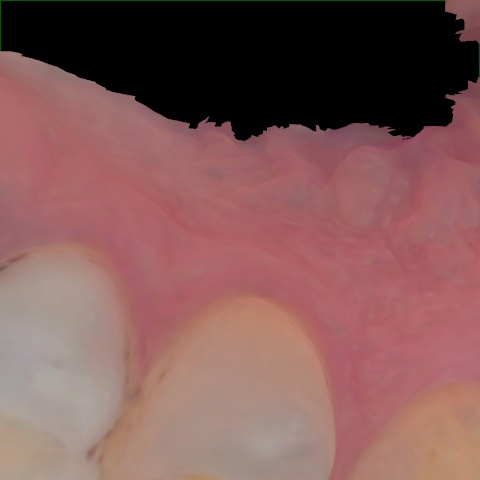

Annotated as "Good"

Original Image Rendering Image